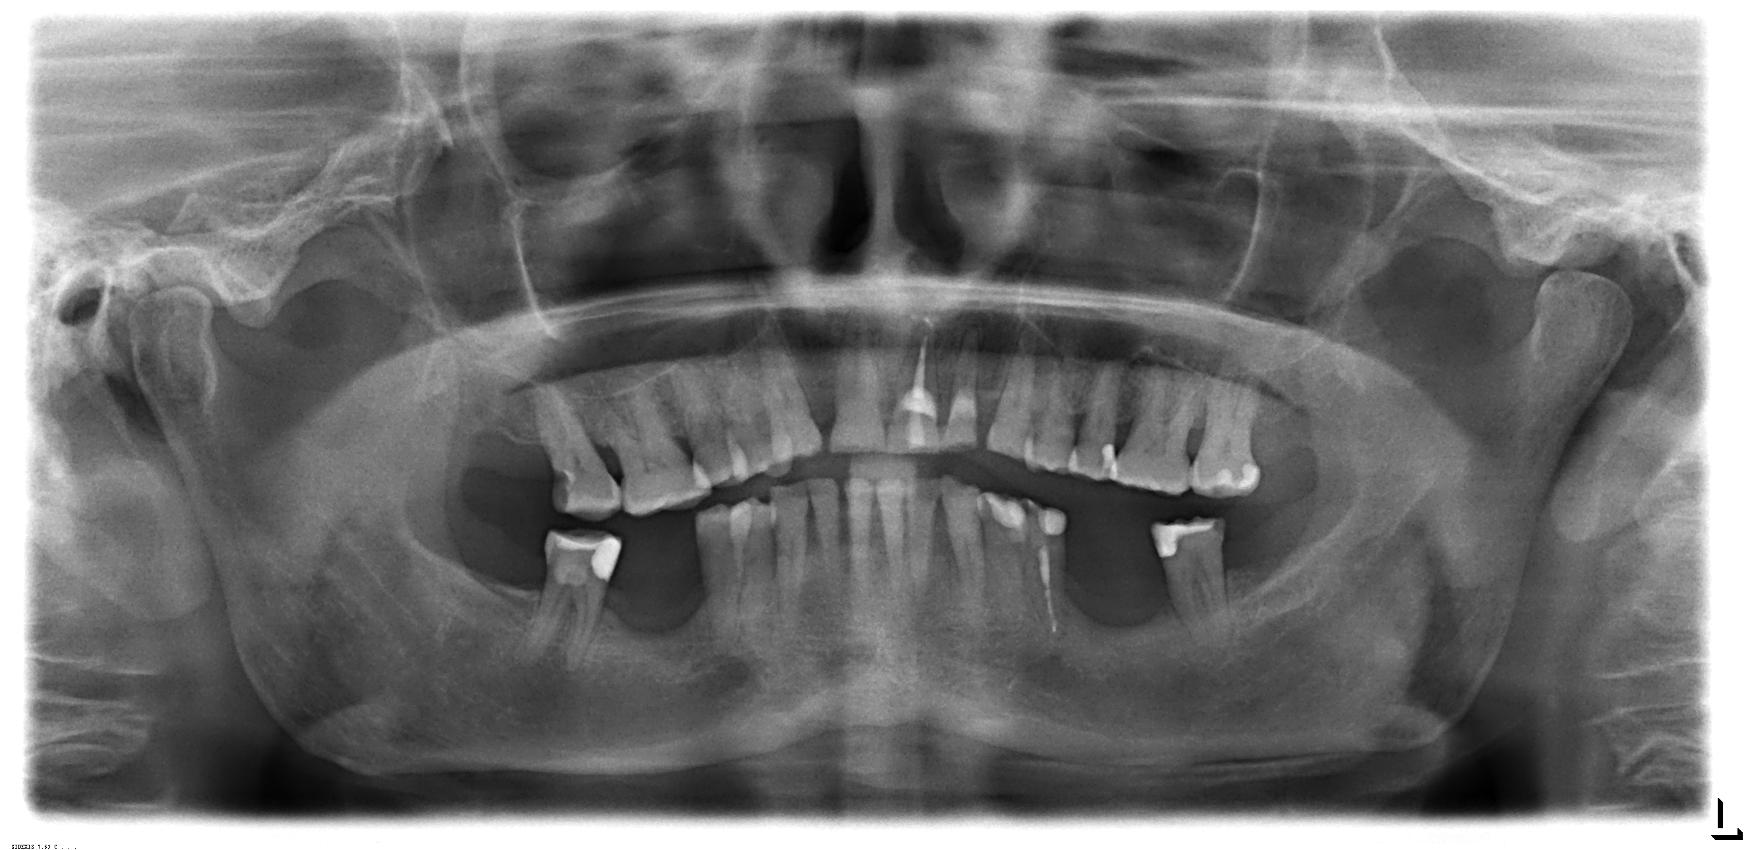

2 Implantate setzen mit Kronen

Gesetzlicher Heil- und Kostenplan

I. Befund des gesamten Gebisses / Behandlungsplan

Oberkiefer

Unterkiefer

Bemerkungen (bei Wiederherstellung Art der Leistung)

Besonderheiten

• mit Freilegung

• mit Auswechseln der SekundĂ€rteile

• Knochenaufbau: 2x keine Angabe

• Knochenentnahme: 2x keine Angabe

• 4050, 4055